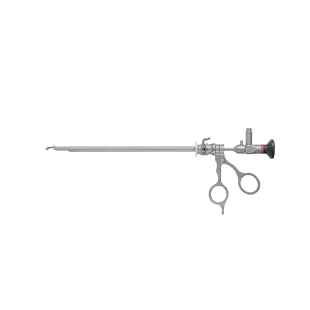

요관 경성 내시경

요관 경성 내시경 -